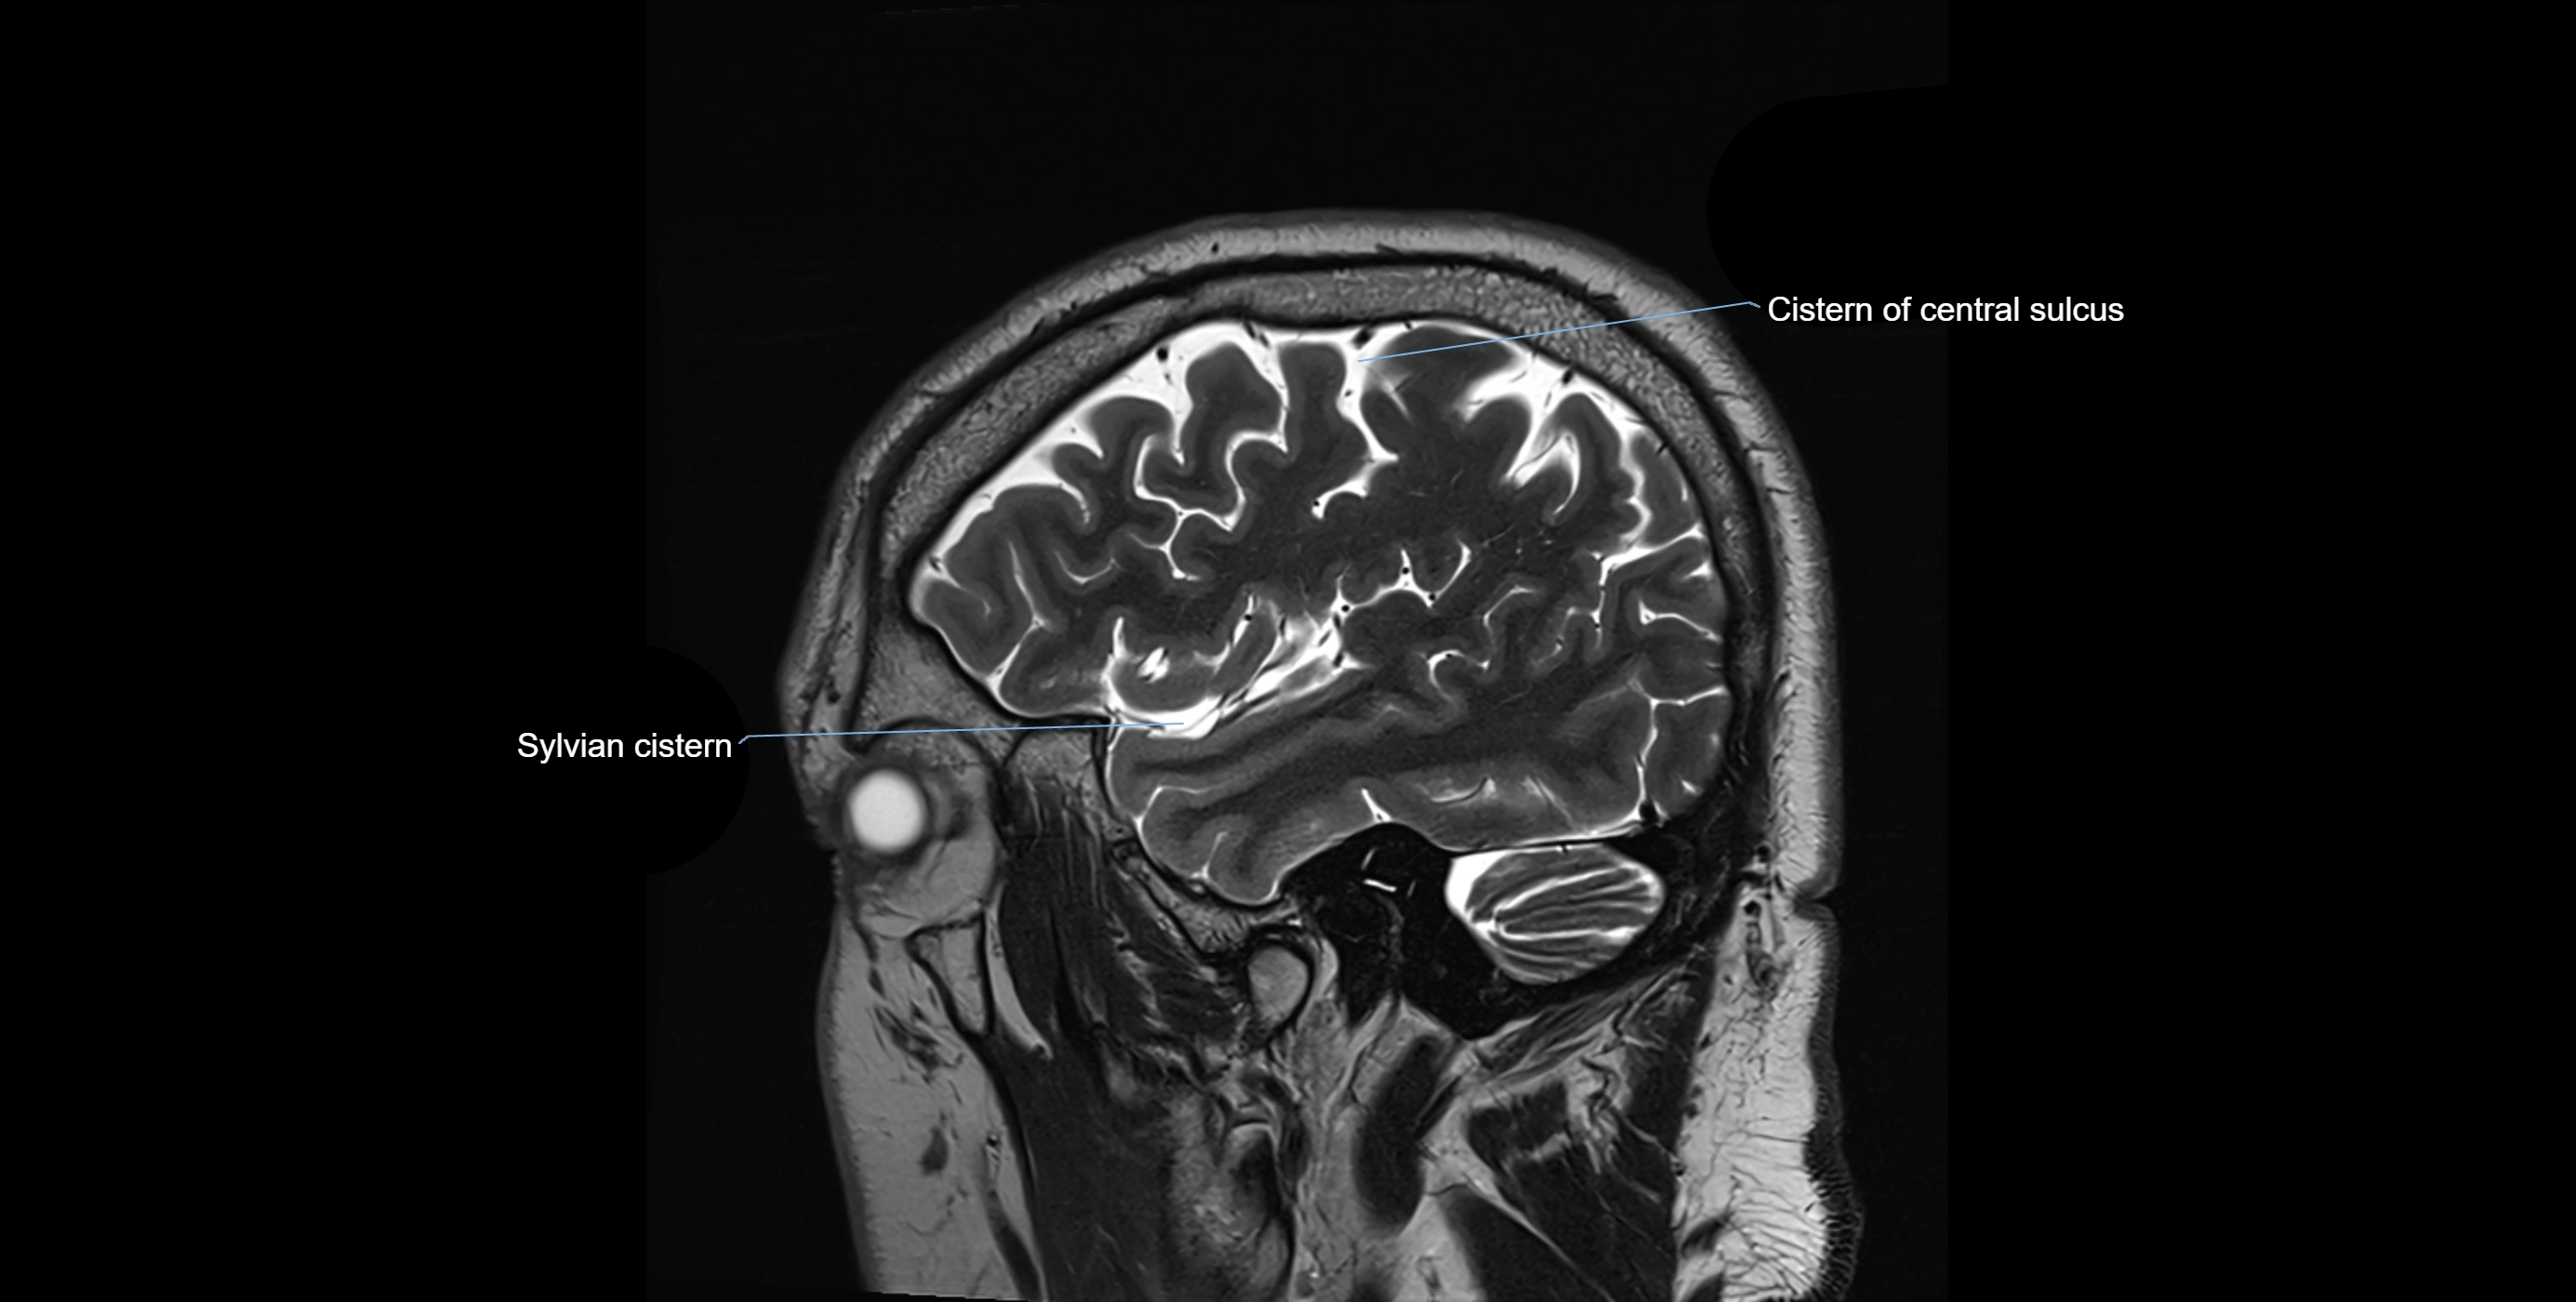

CT image

image